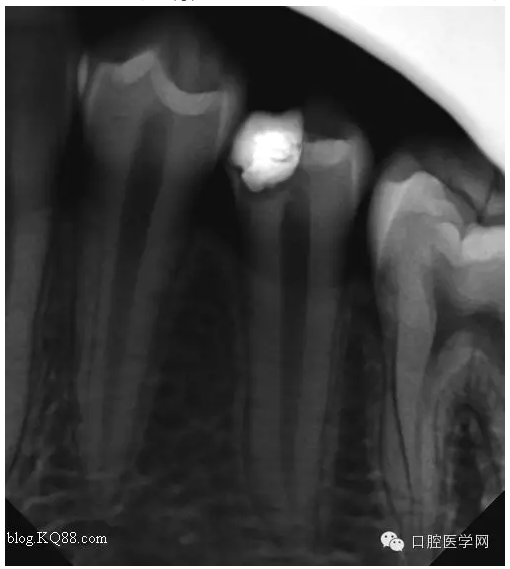

三個月后復(fù)查:高聳的髓角消失。形成約1mm的修復(fù)性牙本質(zhì)?;佳罒o癥狀,溫度測試同對照牙。此時修復(fù)性牙本質(zhì)的形成已趨于穩(wěn)定。每次復(fù)查的溫度測試是判斷牙髓活力,有時雖然沒有臨床癥狀,但牙髓受到慢性刺激會無痛性漸進(jìn)性壞死。導(dǎo)致保存活髓失敗。

所以每次復(fù)查的溫度測試必不可少的。

最后的充填我是這樣做的:去除部分暫封物。直接樹脂充填。